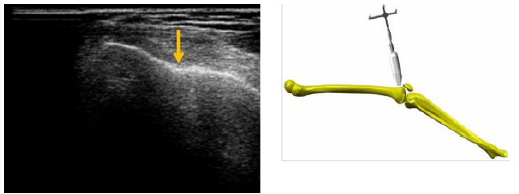

Trochlea groove, intercondylar notch and tibial tuberosity were detected from cranial to caudal. The subject was sitting in 60 degrees of knee flexion. The probe was first placed transversely above the patella and tilted from caudal to cranial until the depth reaches its maximum. The deepest point of the echogenic structure is the trochlea groove (Figure 3). Next, the probe was positioned directly under the patella. The intercondylar notch becomes visible (Figure 4). This distinctive landmark is the deepest point of femoral articulation surface. Transversally, the tibial tuberosity was localized at the proximal tibia. The high point of this land- mark is in evidence (Figure 5).